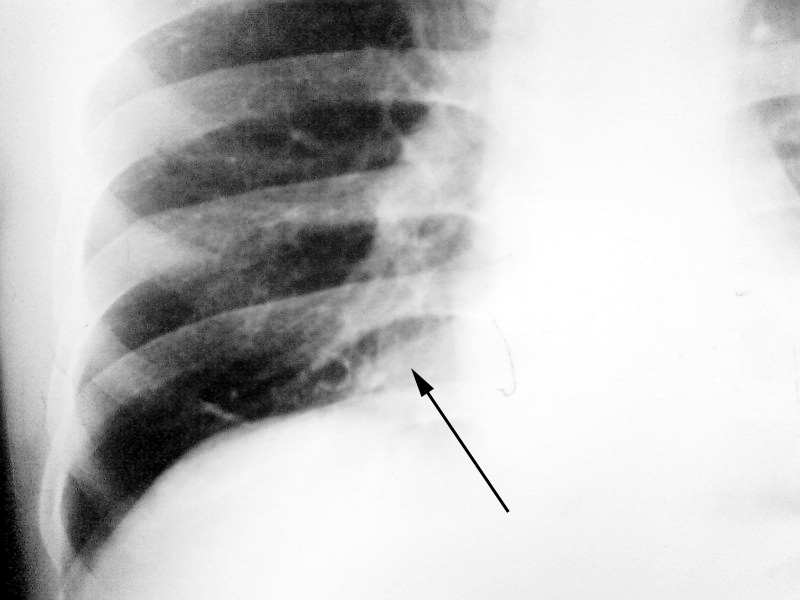

以下是引用yangzhenghai在2008-11-1 8:31:00的发言:[br]对,应该是脂肪垫。

以下是引用zhangzhongshou在2008-11-1 12:00:00的发言:[br]多可能为下腔静脉[br]